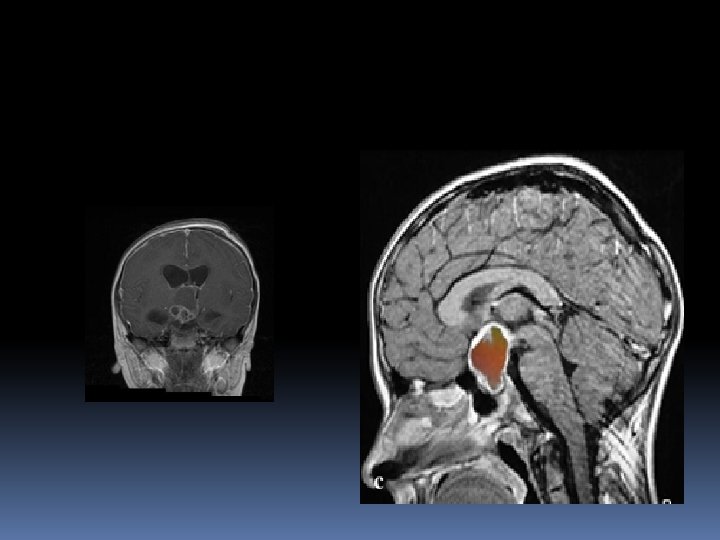

Neuroimaging studies C. T SCAN of sella with thin slices(1. 5 -2 mm)plus contrast , to exclude ac. Haemorrhage. MRI of sellar & parasellar(<2. 5 mm slices) Cerebral angiography or MRI angio to exclude aneurysms.

A conservative approach is usually recommended in incidentally detected lesions, which became more frequent with the widespread availability of MR imaging. BUT the progression of a tumour, which is clearly documented in the MR, is another indication to surgically attack a lesion that has already shown an increase in size.